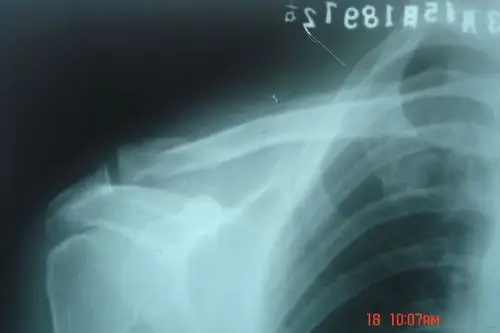

一例锁骨骨折合并肩峰骨折的治疗

左侧锁骨肩峰端见不规则透亮线,骨折处稍移位,左侧锁骨骨折.

一例锁骨近端骨折和肩峰骨折,大家看看